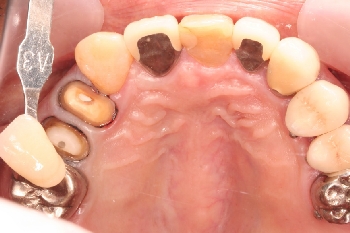

千葉県木更津市 K.Y様 右上45番 メタルボンドクラウン修復

担当歯科医師:丸林浩太郎